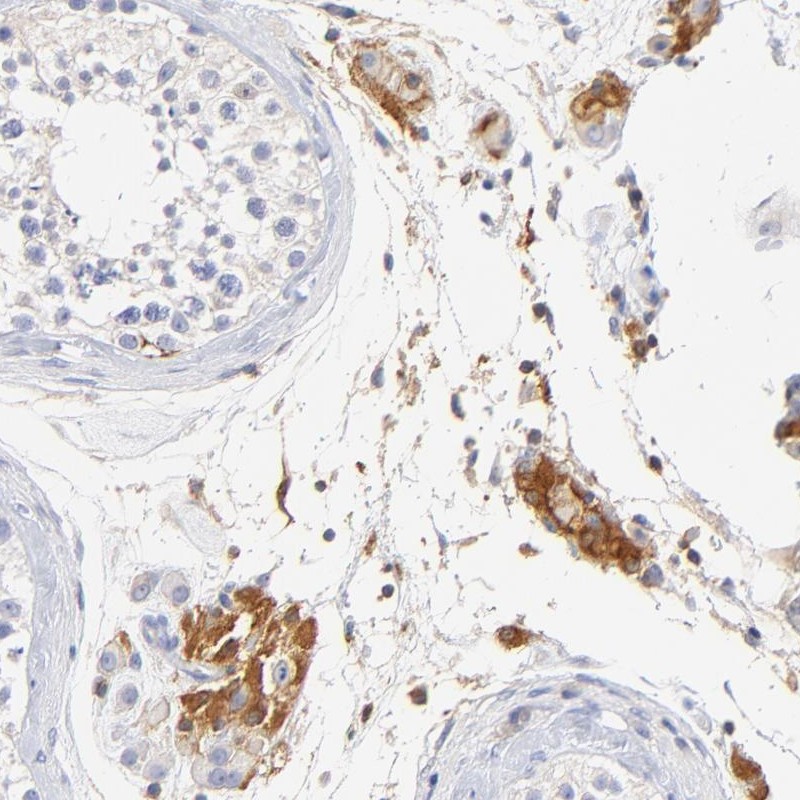

Immunohistochemical staining of human testis shows strong cytoplasmic positivity in Leydig cells.